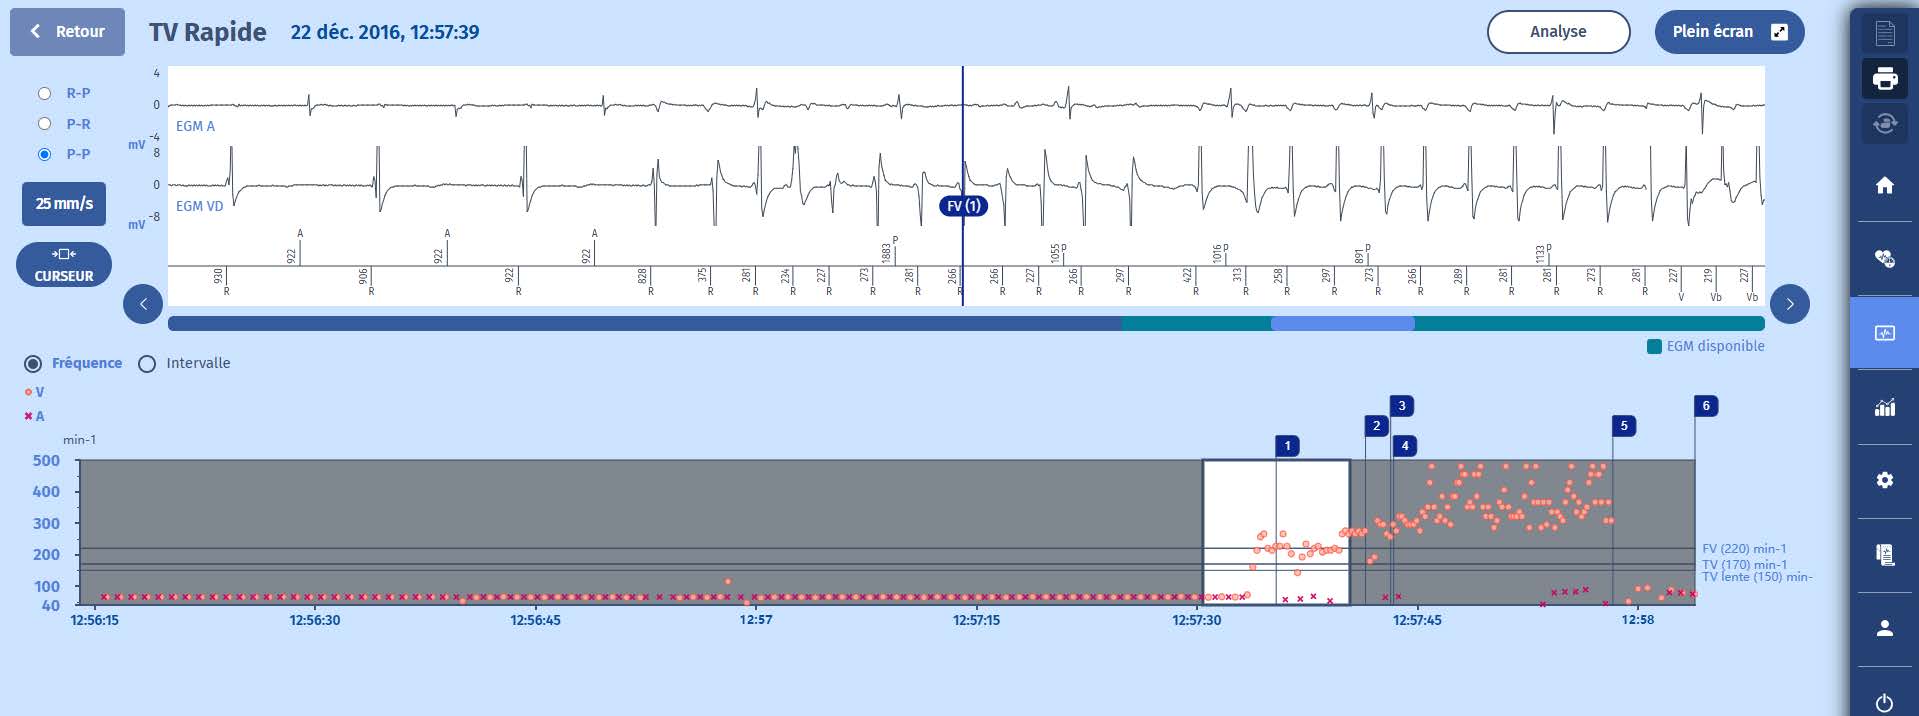

Cet exemple explique la séquence des thérapies dans la zone TVR/FV.

1 La tachycardie est immédiatement détectée dans la zone de FV après 8 cycles de tachycardie. On peut voir que la tachycardie n'est pas stable au départ.

2 Une persistance de 16 cycles est donc déclenchée au terme de laquelle

3 la première thérapie dans la zone TVR est initiée puisque la tachycardie est encore dans la zone FV à la fin de la persistance avec un rythme stable : la thérapie délivrée est un burst de 8 cycles.

4 Cela dégrade la tachycardie en une fibrillation ventriculaire, d'abord observée dans la zone TV (marqueur VTLC) puisque les deux premiers cycles après la SAT sont plus longs et diagnostiqués comme FV au cycle suivant (marqueur FV), d'où le déclenchement

d'une nouvelle persistance de 16 cycles.

5 La deuxième ligne de thérapie consiste en des chocs, d'où la charge des condensateurs.